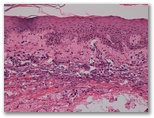

1533- Paciente varón de 64 años, con linfadenopatia generalizada, hepatoesplenomegalia,, e hipergamaglobulinemia. La analítica muestra inmunocomplejos circulantes, y crioaglutininas. La biopsia ganglionar muestra una marcada proliferación de vasos venulares en las zona paracorticales.. El motivo de la consulta es la erupción cutánea ilustrada.

4. Reacción tipo toxicodermia asociada a linfadenopatia angioinmunoblastica